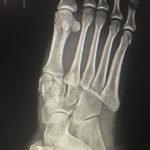

The frontal view of the right foot showed divergent dislocation of the second through fifth metatarsal bones (red outlines) consistent with Lisfranc injury. Though the Lisfranc ligament is not visualized by radiograph, the yellow markings represent the location of the Lisfranc ligament between the medial cuneiform (blue dot) and the base of the second metatarsal bone. The first metatarsal and the medial cuneiform remain congruent. The lateral view shows dorsal dislocation of the midfoot (pink circle) consistent with instability. There is associated extensive midfoot soft tissue swelling.